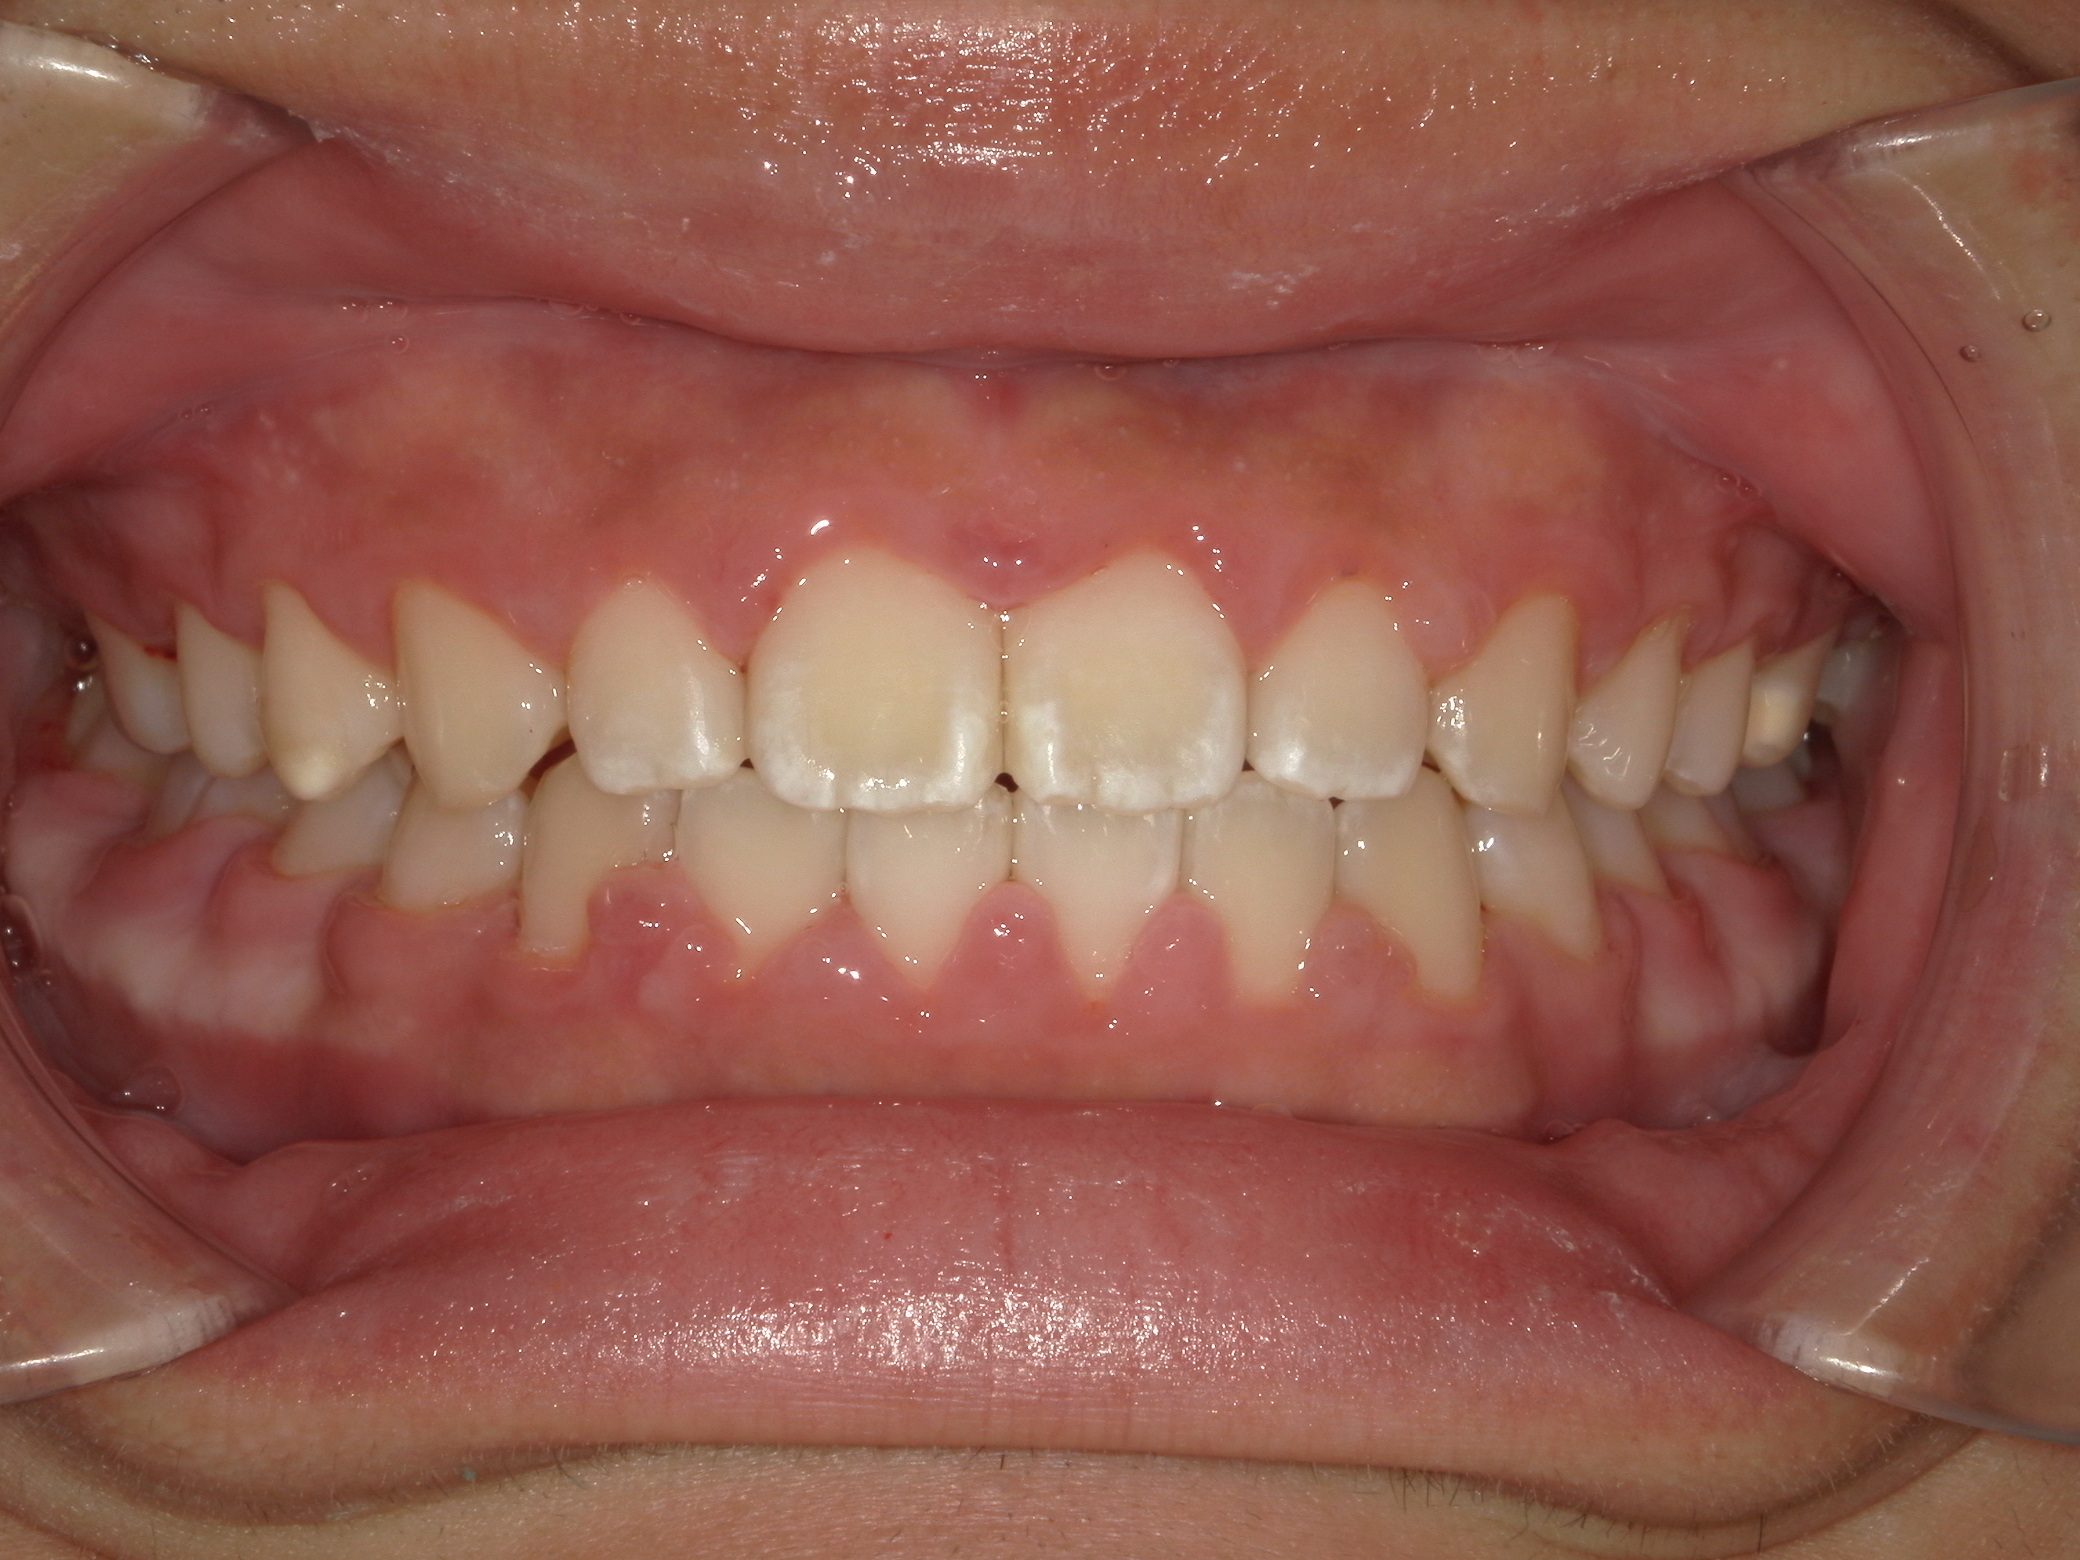

歯の位置異常(犬歯位置異常)

8歳 男性

歯列弓拡大、前歯の正常被蓋獲得、犬歯の誘導

拡大床、部分ワイヤー

495,000円(税込)

2年6か月

左上犬歯の位置異常が初診時検査で認められました。外科的誘導は行っておらず、歯列弓をしっかり拡大し、乳歯を意図的に抜歯してあげることで本来の位置へ誘導することに成功しています。矯正歯科医院での適切な判断で外科処置を回避できた症例です。

2期治療にて仕上げの矯正治療を行う予定です。